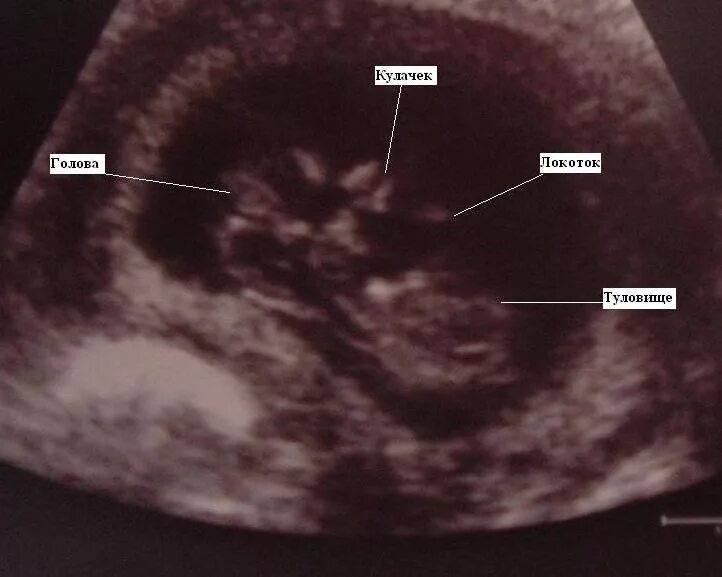

12 недель и два дня